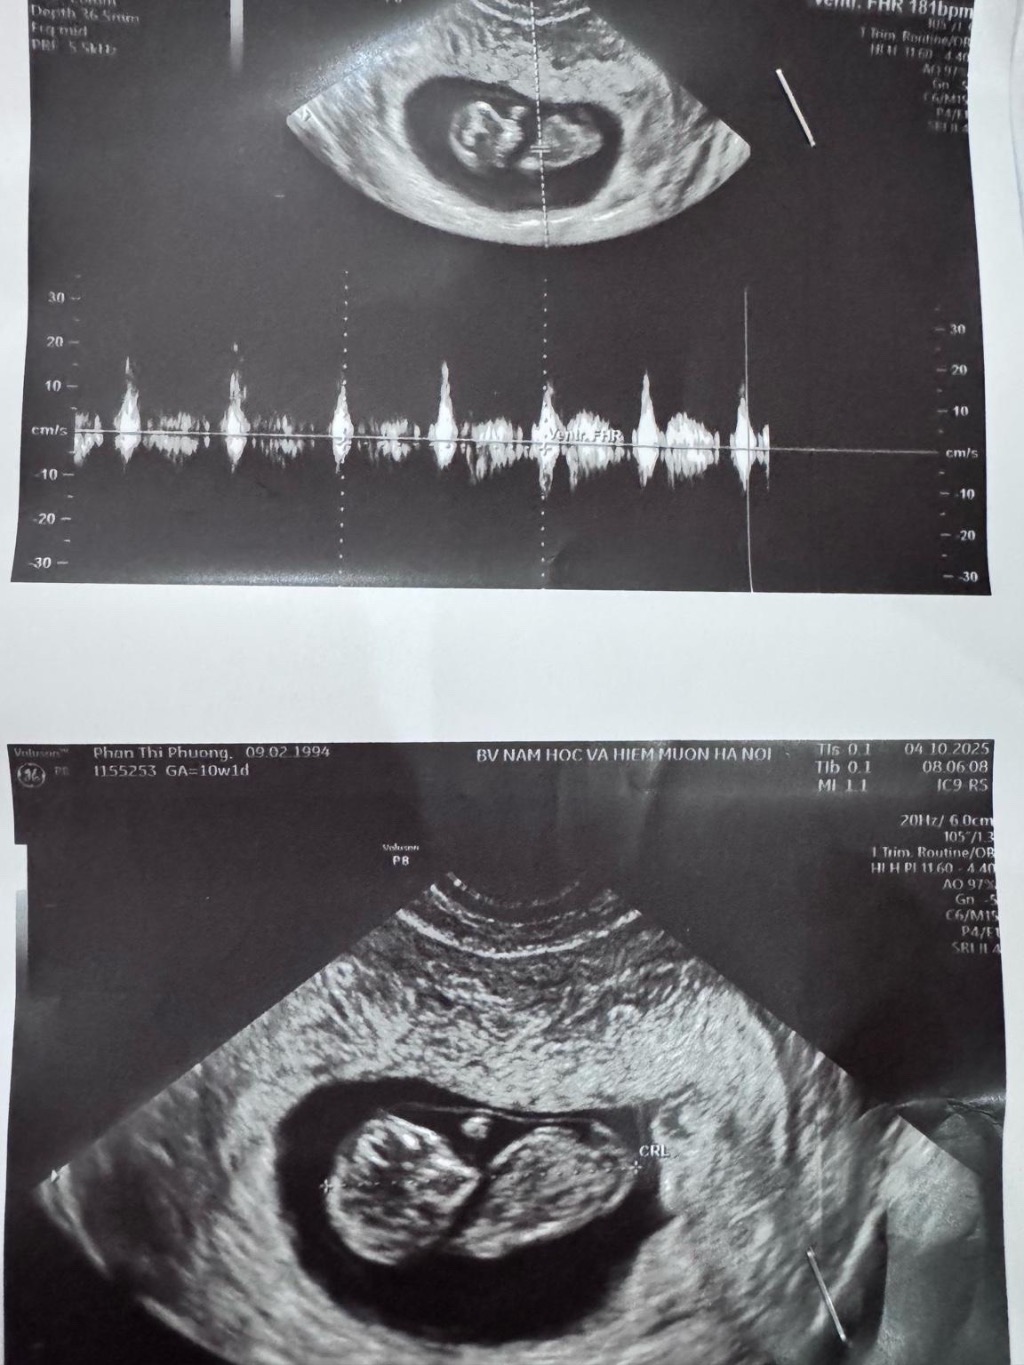

Phan Thị Phương